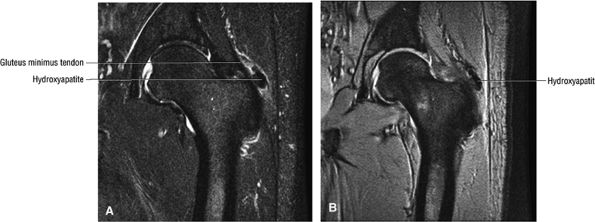

FIGURE 3.30 ● Normal sagittal anatomy of the hip. (A and B) On medial sagittal images, the course of the obturator internus, piriformis, and the adductor muscles can be followed and analyzed for strain injury or tears. (C and D) Tendinosis and tears of the common hamstring tendon origin on the ischial tuberosity are optimally viewed at this location and are extremely common in middle aged and elderly patients. (E and F) Although thinning and fraying of the articular cartilage can occur anywhere in the joint, chondral degeneration is most commonly seen first in the anterior superior quadrant, often accompanied by anterior labral tears, subchondral edema, and cystic change in the anterior acetabulum. When any one of these findings is present, a careful search for the others should be performed. (G and H) Linear tears of the anterior labrum can be mimicked by fluid filling a normal recess between the anterior labrum and the anterior joint capsule. Imaging in the axial and coronal planes is used to distinguish between a true tear and the normal recess, since a tear is visualized and confirmed in the axial and coronal planes, whereas a recess is only seen prominently in the sagittal plane. (K and L) The gluteus medius and minimus tendons have been referred to as the “rotator cuff” of the hip. The gluteus medius tendon inserts posteriorly on the greater trochanter, and the gluteus minimus tendon inserts anterolaterally on the greater trochanter. (I and J) Loose bodies commonly lodge in the joint recesses anterior and posterior to the femoral neck (deep to the iliofemoral and ischiofemoral ligaments). They are commonly seen (particularly in the sagittal plane) in patients with chondral degeneration. (M and N) Acute tears of the gluteus medius and minimus often mimic symptoms of a proximal femoral fracture. Chronic partial tears and tendinosis are frequently associated with trochanteric bursitis, and are common in middle-aged and elderly patients.